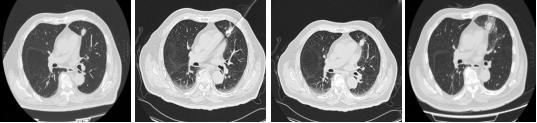

从手术开始到结束,仅耗时35分钟。陈老伯安返病房,生命体征平稳。术后陈老伯状态良好,CT显示病灶区域密度增高,消融范围完美覆盖了病灶,而周边的肺组织安然无恙。

消融前、消融中、消融中、消融后一天